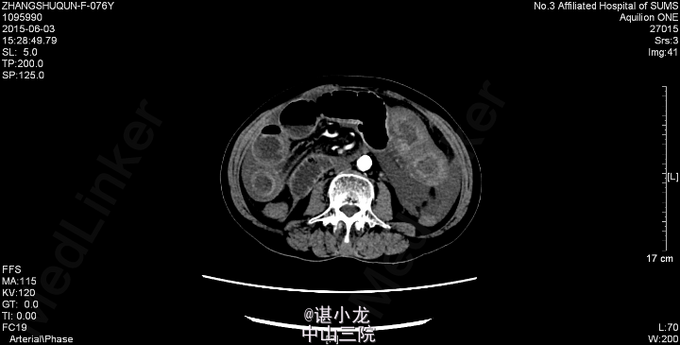

腹平坦,腹部未见曲张静脉、色素沉着,未见手术疤痕,未见胃型、肠型,腹肌软,全腹部压痛、反跳痛,未触及包块,腹部叩诊呈鼓音,肝脾肋下未触及,Murphy(-),肝浊音界叩诊不清,肝区、双肾区无叩痛,腹部移动性浊音(-),肠鸣音3-4次/分。直肠指检未扪及肿物,退指套无血染。 2015-6-3我院急诊腹部CT:空肠扭转,并小肠壁广泛水肿、增厚;腹盆腔中量积液。腹主动脉、双侧髂动脉、双肾动脉、脾动脉硬化。 血常规:白细胞总数16.490x10E9/L,中性粒细胞百分率0.877。凝血四项:凝血酶原时间>200.000sec,活化部分凝血酶时间>180.000sec。大便潜血试验阳性。肝功未见异常,生化示低钠131mmol/L,肌酐260umol/L。